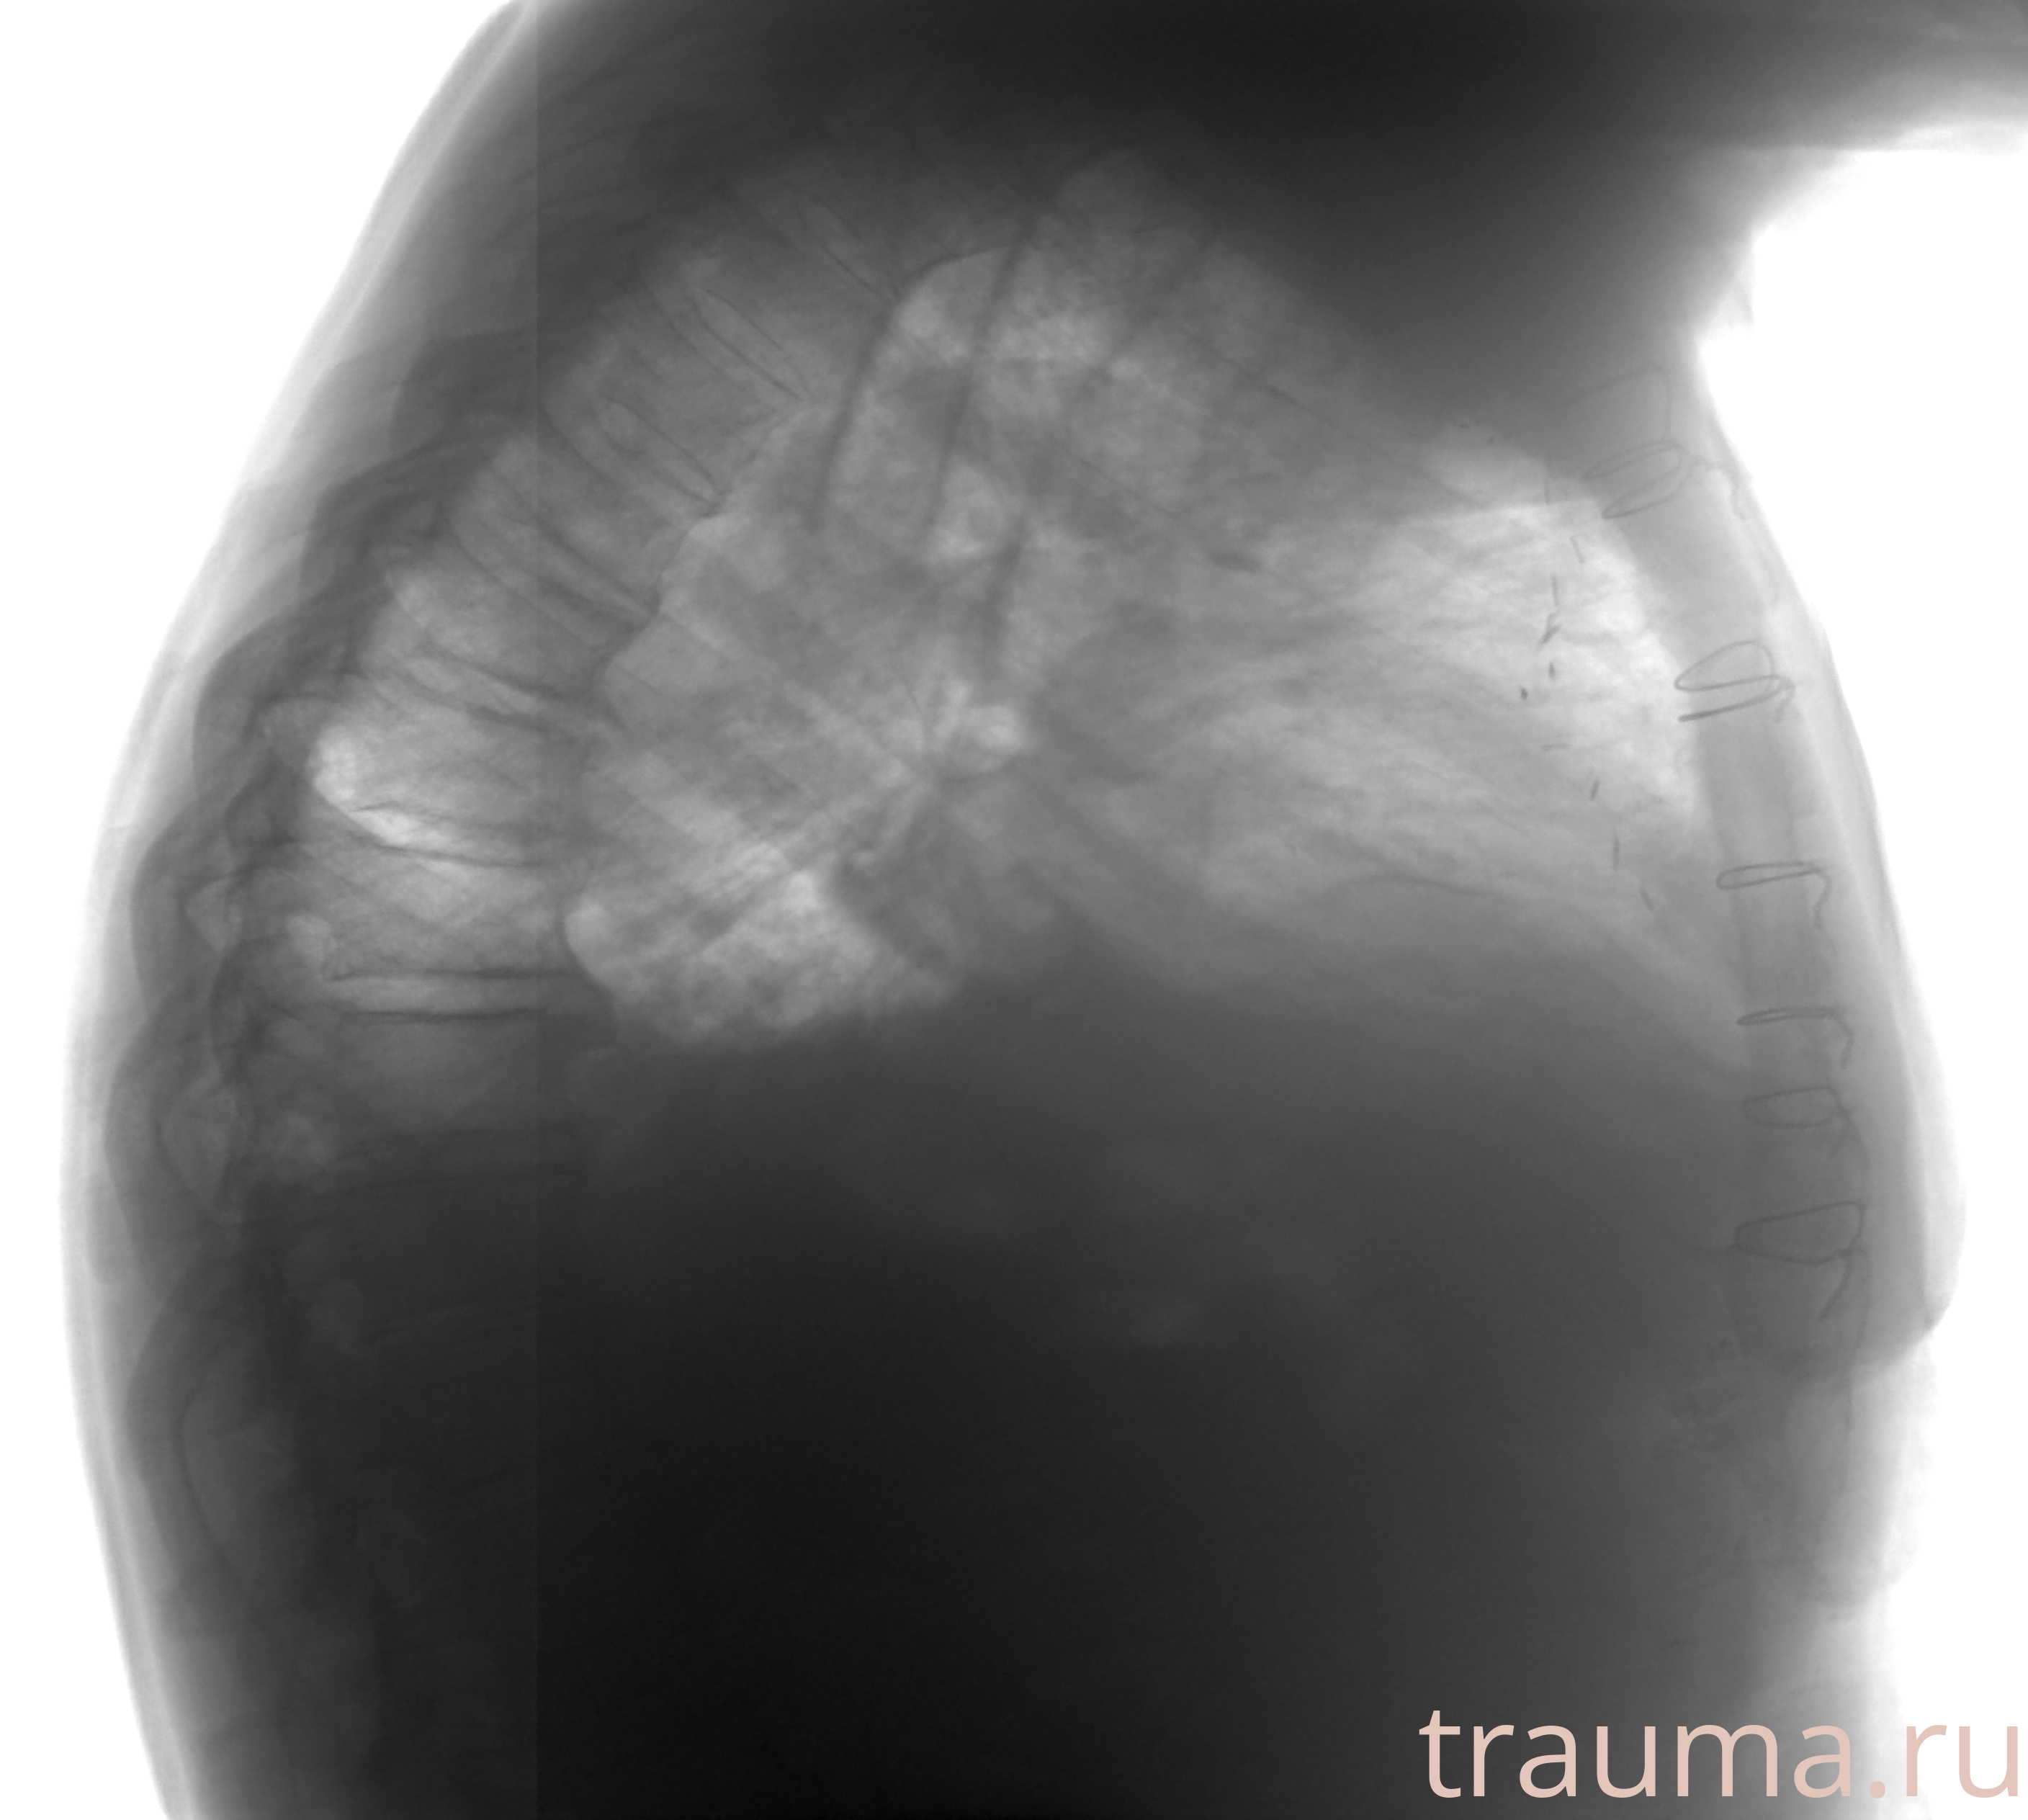

Рентген на дому: по вашему адресу приезжает врач-рентгенолог, травматолог-ортопед с мобильным рентгеновским аппаратом, проводит диагностику травмы или заболевания, делает необходимые рентгенограммы, дает рекомендации по дальнейшему лечению. Получить качественные снимки в домашних условиях возможно благодаря уникальной методике, разработанной МосРентген Центром для института  Склифосовского